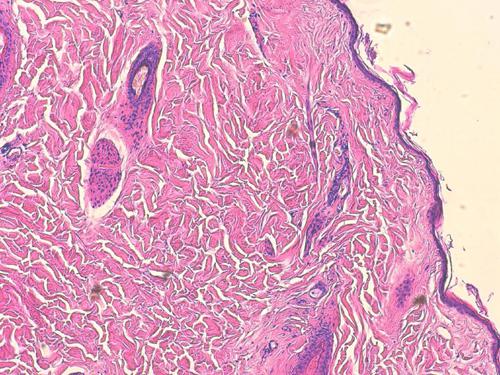

Photo 6 : épiderme et annexes atrophiés (photo F. Degorce)

La jonction dermo-hypodermique est très difficile à percevoir car au sein de l’hypoderme, on observe en fait une hyalinisation et un épaississement des travées conjonctives et des espaces périvasculaires et péri nerveux, ces épaississements se traduisent par une hyalinisation d’aspect discrètement cellulaire. Pas de mise en évidence d’élément figuré pathogène ni parasitaire ni fongique.

Photo 7 : hyanilisation et épaississement

des travées conjonctives (photo F. Degorce)

L’épiderme est atrophié. Au sein des unités annexielles folliculo-sébacées, les annexes sont dans l’ensemble nettement atrophiées et particulièrement les follicules pileux. Ceux-ci, qu’ils soient secondaires ou primaires, sont majoritairement en phase télogène et catagène et expriment une kératinisation trichilemmale très accentuée. Certains follicules persistants sont actifs et en phase anagène. Le derme n’est pas inflammatoire.